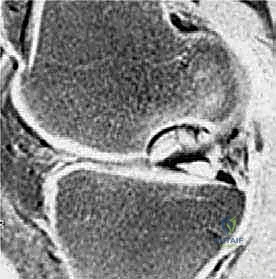

3. التصوير بالرنين المغناطيسي (MRI) – المعيار الذهبي

لا يمكن تقييم الغضروف المفصلي بدقة باستخدام الأشعة السينية. هنا يأتي دور الرنين المغناطيسي العالي الدقة. يُعد الرنين المغناطيسي حجر الزاوية في خطة الأستاذ الدكتور محمد هطيف التشخيصية، حيث يسمح بـ:

* تقييم حالة الغضروف المفصلي (هل هو سليم، متورم، أم ممزق؟).

* تحديد مدى ثبات القطعة العظمية (في حالات OCD). وجود سائل بين القطعة والسرير العظمي في صور T2 يشير إلى عدم الاستقرار.

* اكتشاف الوذمة العظمية (Bone Marrow Edema) التي تميز حالات SONK و AVN في مراحلها المبكرة قبل ظهورها في الأشعة السينية.

* تحديد حجم وعمق الآفة بدقة مليمترية للتخطيط الجراحي.